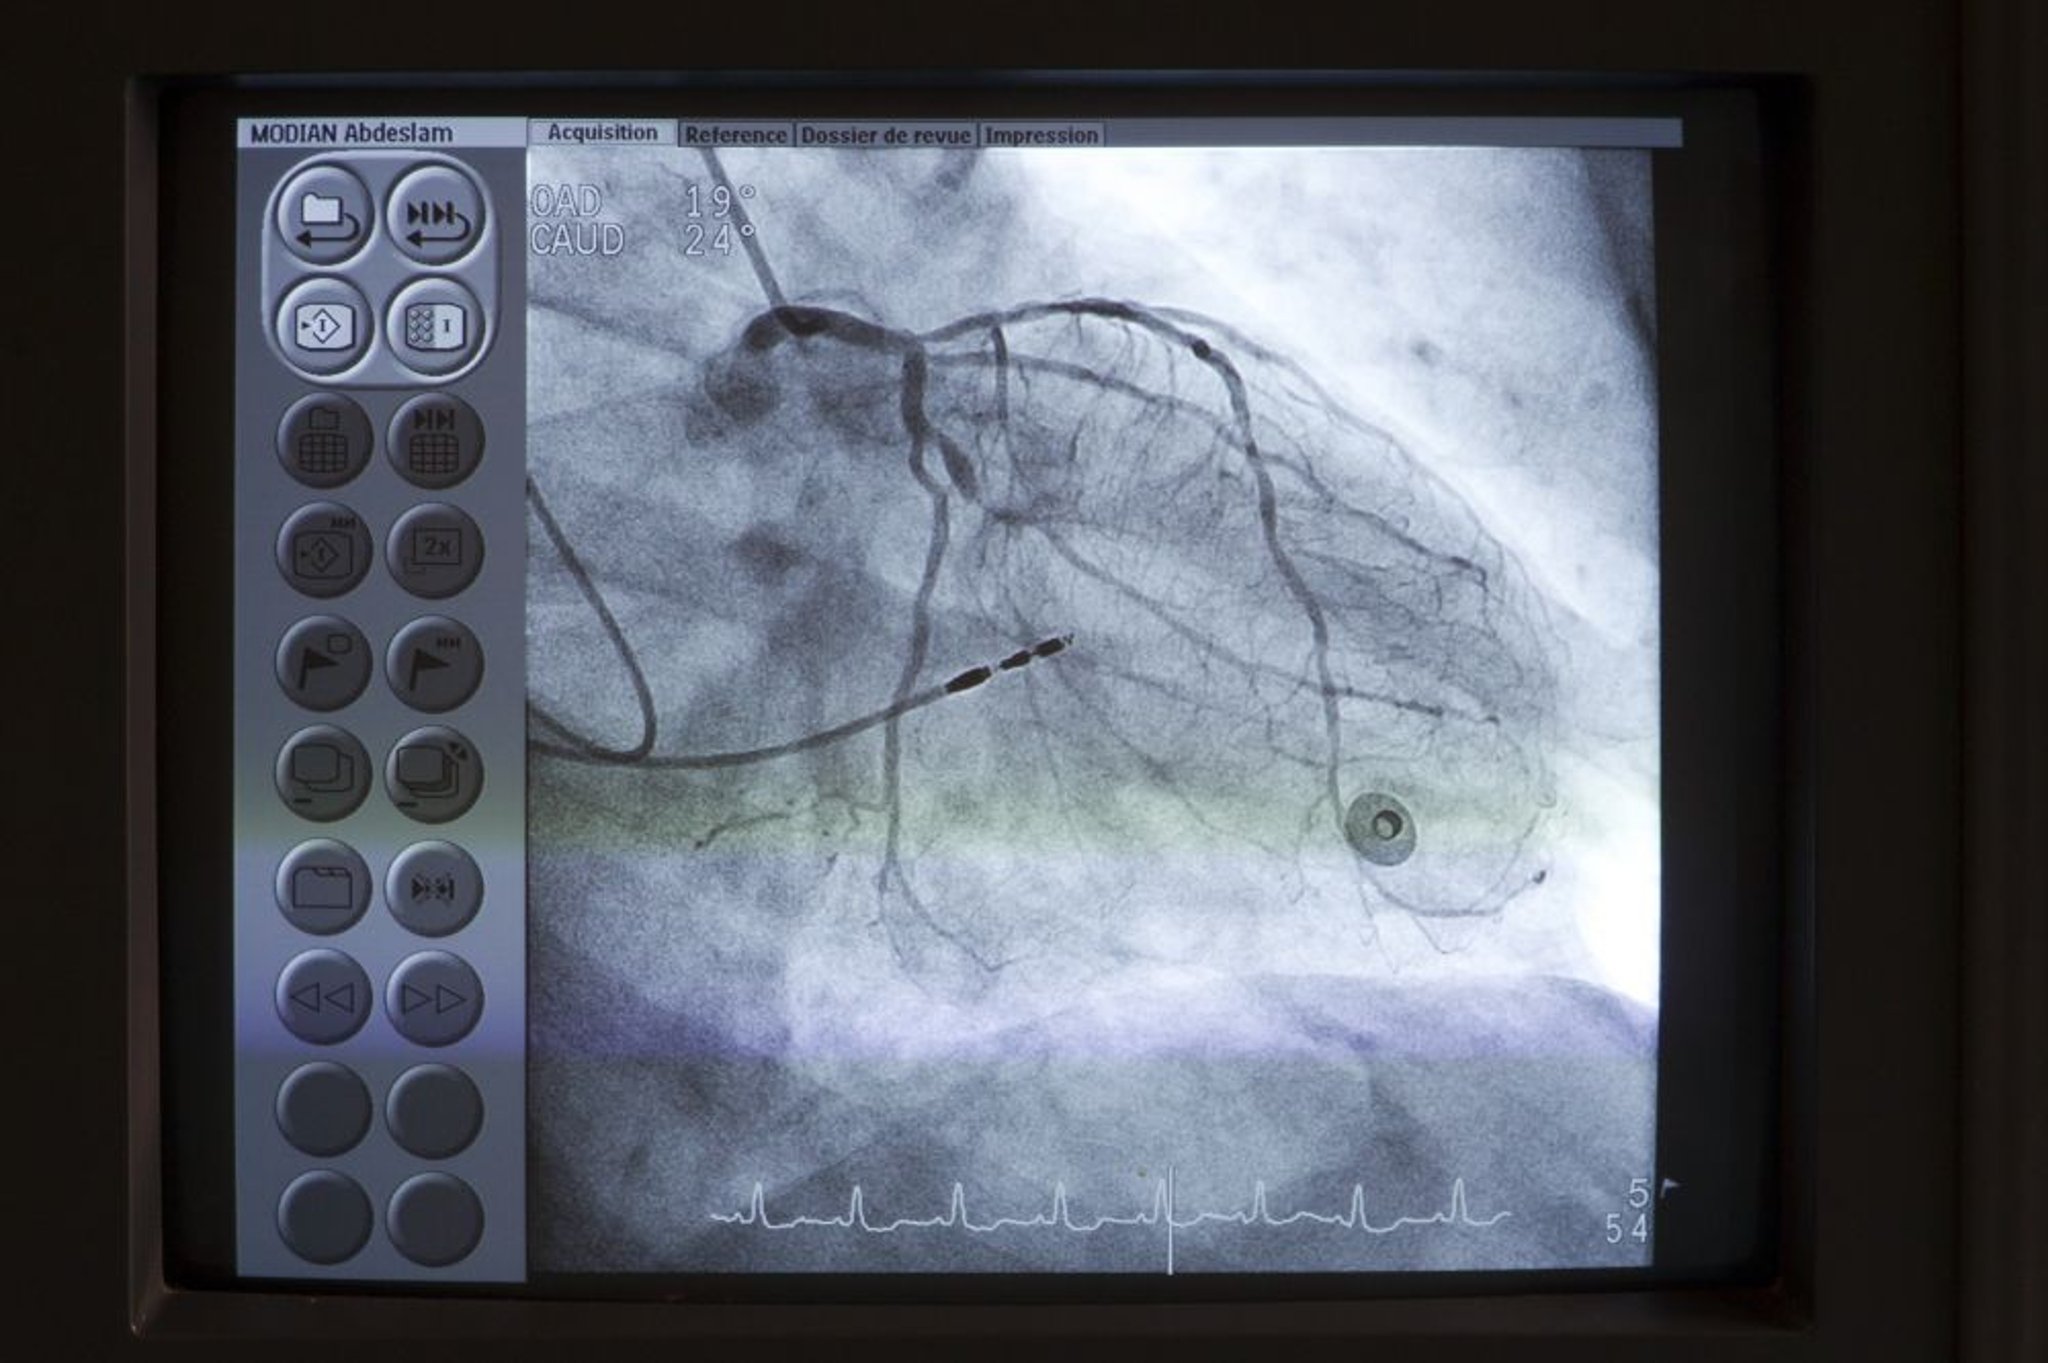

Chụp mạch vành

Một ống thông (phía trên bên trái) được đặt ở đầu của động mạch vành trái. Thuốc cản quang sau đó được tiêm vào động mạch vành dưới màn soi huỳnh quang để phát hiện bất kỳ dị thường nào như hẹp mạch vành.

Astier/BSIP/SCIENCE PHOTO LIBRARY